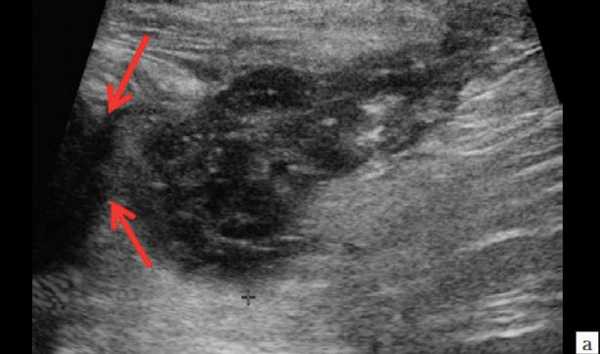

УЗИ мягких тканей шеи

Ультразвуковое исследование рассматриваемой анатомической области чаще проводят с целью визуализации дополнительных образований. Сонография позволяет разграничить инфекционный, сосудистый, опухолевый характер патологического процесса.

Во многих клиниках в протокол УЗИ мягких тканей шеи включают сканирование лимфатических узлов, определение структуры которых помогает дифференцировать воспалительные, доброкачественные, метастатические поражения при вирусных и бактериальных заболеваниях ЛОР-органов, лейкозах, раке легких, молочной железы, гортани и др.